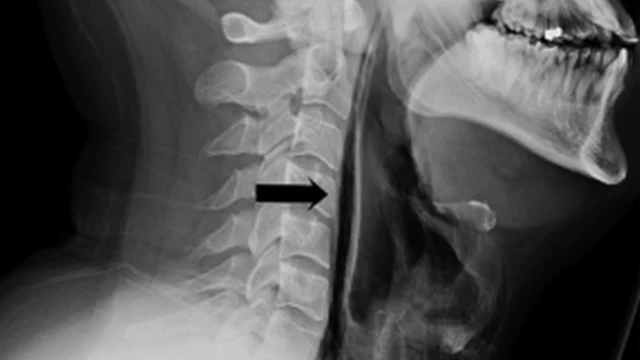

Asalin hoton, BMJ

Wannan hoton da aka dauka ya nuna yadda iska ta yi tsalle daga makogwaronsa ta shiga cikin fata.